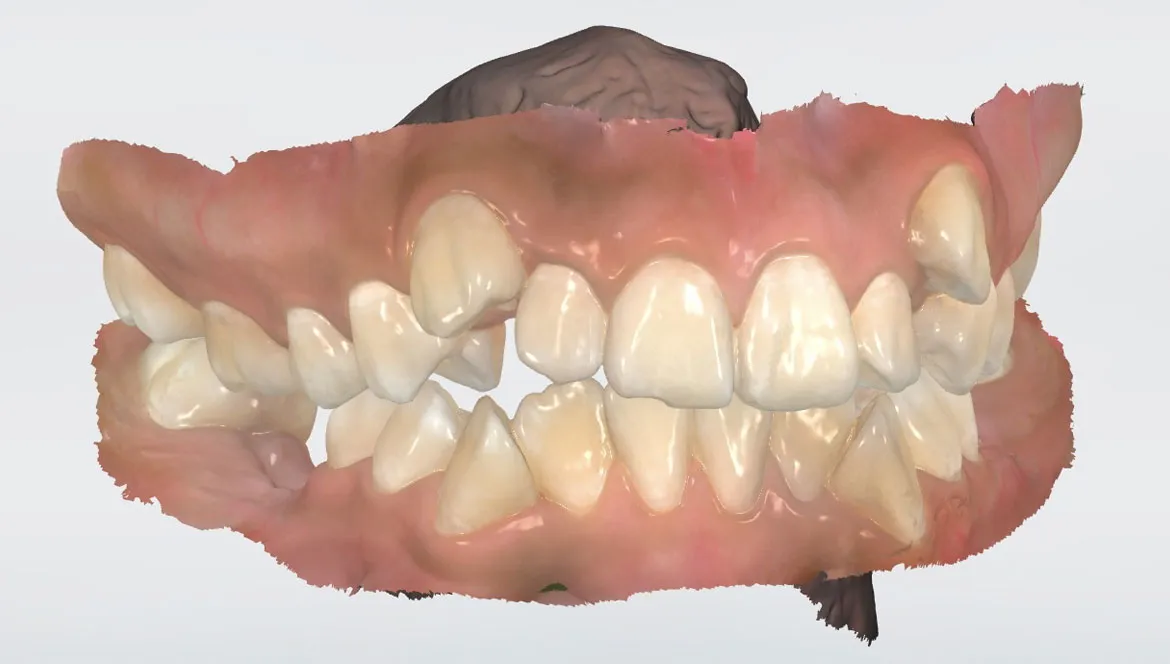

ESCANEO INTRAORAL

Con nuestro escáner de la marca 3Shape captura impresiones directamente sobre la dentadura obteniendo una imagen en 3D, eliminando el sistema tradicional de impresiones físicas realizadas con alginato.

IMPRESIONES 3D

Modelos dentales en un tiempo más corto y con mayor precisión, lo que beneficia tanto a los pacientes como a los profesionales.

Escaneo de maxilar superior e inferior indicado para tratamiento de ortodoncia.